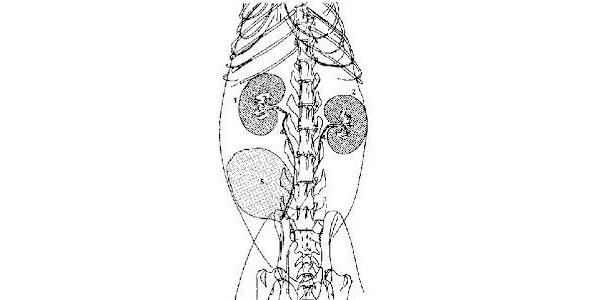

Мал. 2. Сечовидільна система [12]

Сечовивідні органи включають ниркову балію, сечоводи, сечовий міхур і сечівник. Всі сечовивідні органи вистелені перехідним епітелієм, який утворює надійний бар'єр для сечі під підвищеним тиском.

Сечовід є шкірно-м'язову трубку і складається з адвентиційної, м'язової та слизової оболонок. Зсередини сечовода, як і ниркова балія, вистелена перехідним епітелієм.

Сечовий міхур дуже еластичний, особливо у собак. Розрізняють тіло сечового міхура та розташовану краніальну верхівку, а каудально — шийку. Незалежно від наповнення сечового міхура його тіло завжди лежить у черевній порожнині перед лонним гребенем. Тому він завжди пальпується та легко доступний для оперативних втручань. Верхівка сечового міхура, особливо у собак, яких виводять один раз на день, може сягати пупка і далі.

Сечівник самки відносно короткий і широкий. Він тягнеться від внутрішнього отвору сечівника до розташованого на межі піхви і напередодні піхви (сечостатевого передодня) зовнішнього отвору сечовипускального каналу. При цьому сечівник самки проходить між дном таза і піхвою.

Сечівник самця значно довший, ніж у самки; у самців собак і кішок він відрізняється через різну форму і положення статевого члена. Тазова частина сечівника поділяється на передміхурову частину і передміхурову частину. Передміхурову частину тягнеться від внутрішнього отвору сечівника до насіннєвого пагорба, до якого збоку сходять простатичні протоки. На зводі сечівника у цій частині видно його гребінь, що закінчується насіннєвим горбком. У цьому місці в сечівник впадають сім'япроводи і він стає сечостатевим каналом. Передміхурова, або тазова, частина здебільшого охоплюється м'язом сечівника сечостатевого каналу. На виході з тазу тазова частина сечівника переходить у половочленную, або губчасту, частину. У котів місце переходу відзначено бульбоуретральною залозою [12].

Мал. 3. Сечівник виявляє у своїй будові сильні статеві відмінності [12].